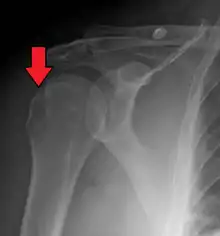

A Hill–Sachs lesion, or Hill–Sachs fracture, is a cortical depression in the posterolateral head of the humerus. It results from forceful impaction of the humeral head against the anteroinferior glenoid rim when the shoulder is dislocated anteriorly.

| Anterior shoulder dislocation on X-ray with a large Hill–Sachs lesion | |

Diagnosis can be suspected by history and physical examination which is usually followed by imaging. Because of the mechanism of injury, apprehension of anterior dislocation is common with provocative maneuvers. Hill–Sachs lesions have been classified as "engaging" or "non-engaging", with engaging lesions defined by the ability of the glenoid to sublux into the humeral head defect during abduction and external rotation. Engaging dislocations have a higher risk of recurrent anterior dislocation, and their presence can help guide surgical management.[2] Imaging diagnosis conventionally begins with plain film radiography. Generally, anteroposterior (AP) radiographs of the shoulder with the arm in internal rotation offer the best yield while axillary views and AP radiographs with external rotation tend to obscure the defect. However, pain and tenderness in the injured joint make appropriate positioning difficult and in a recent study of plain film x-ray for Hill–Sachs lesions, the sensitivity was only about 20%. i.e. the finding was not visible on plain film x-ray about 80% of the time.[3]